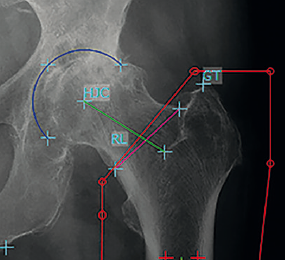

Chức năng femoro-acetabular impingement (“FAI”) trong mô-đun “Hip” tạo điều kiện đo đạc và đánh giá các bất thường về hình thái giải phẫu khớp háng.

Chức năng này cho phép dễ dàng chẩn đoán các bệnh lý, chẳng hạn như các tổn thương hạn chế vận động khớp háng dạng CAM dạng pincer hay dạng kết hợp, cũng như cũng như thiểu sản khớp háng. mediCAD® tạo điều kiện thuận lợi cho việc đo lường và đánh giá chính xác tất cả các thể bệnh FAI trong quá trình tiến triển của bệnh, sử dụng các kỹ thuật chụp X quang khác nhau (Faux-profile, Rippstein, Lauenstein, cross-table lateral view, pelvic view).